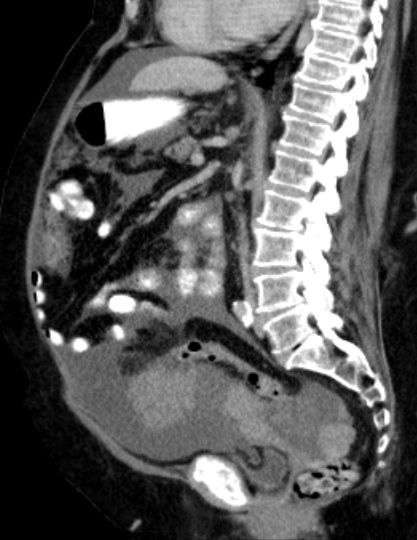

73-jährige Frau mit Ascites, Pleuraerguss links und Unterbauchtumor.  Das Netz ist komplett in einen Omental-Cake umgewandelt. An der Zwerchfellkuppe miliare Tumoraussaat.

Beide Adnexe in knapp kindskopfgroße blumenkohlartige Tumoren umgewandelt.

Im Douglas finden sich pararektal mehrere bis zu pflaumengroße Tumorknoten.